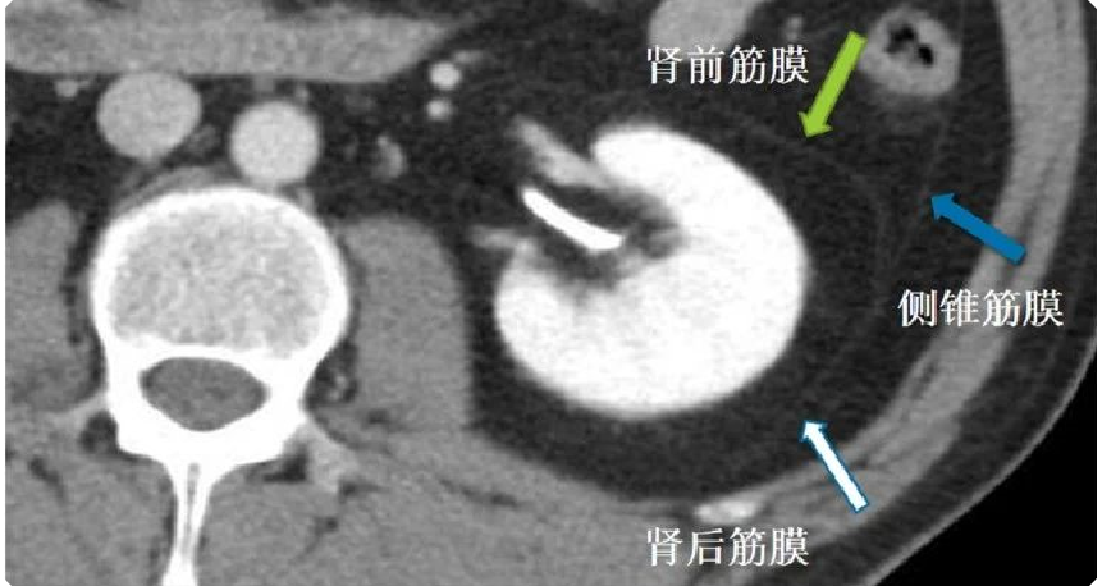

以肾前筋膜(Gerota筋膜)和肾后筋膜(Zuekerkandl筋膜)为分界线,将腹膜后间隙分为肾旁前间隙、肾周间隙和肾旁后间隙。

b4607d7c85e765b30e93581630e601b8.png 图 5:肾前筋膜、肾后筋膜和侧锥筋膜的CT影像